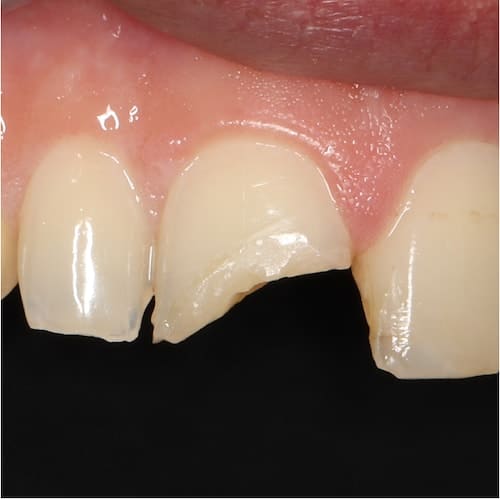

Repairing

Broken Teeth

Breaking a tooth or teeth can be painful and unsightly. It can really knock your confidence and you will want to get it fixed quickly. There are a number of ways to repair a broken tooth and this will depend on such things as how bad the break is, which tooth has been broken and how many teeth are damaged. If you have chipped a tooth it can often be repaired with a filling. If the chip is to one of the front teeth it could be fixed through a process called bonding which uses a tooth-coloured composite resin.